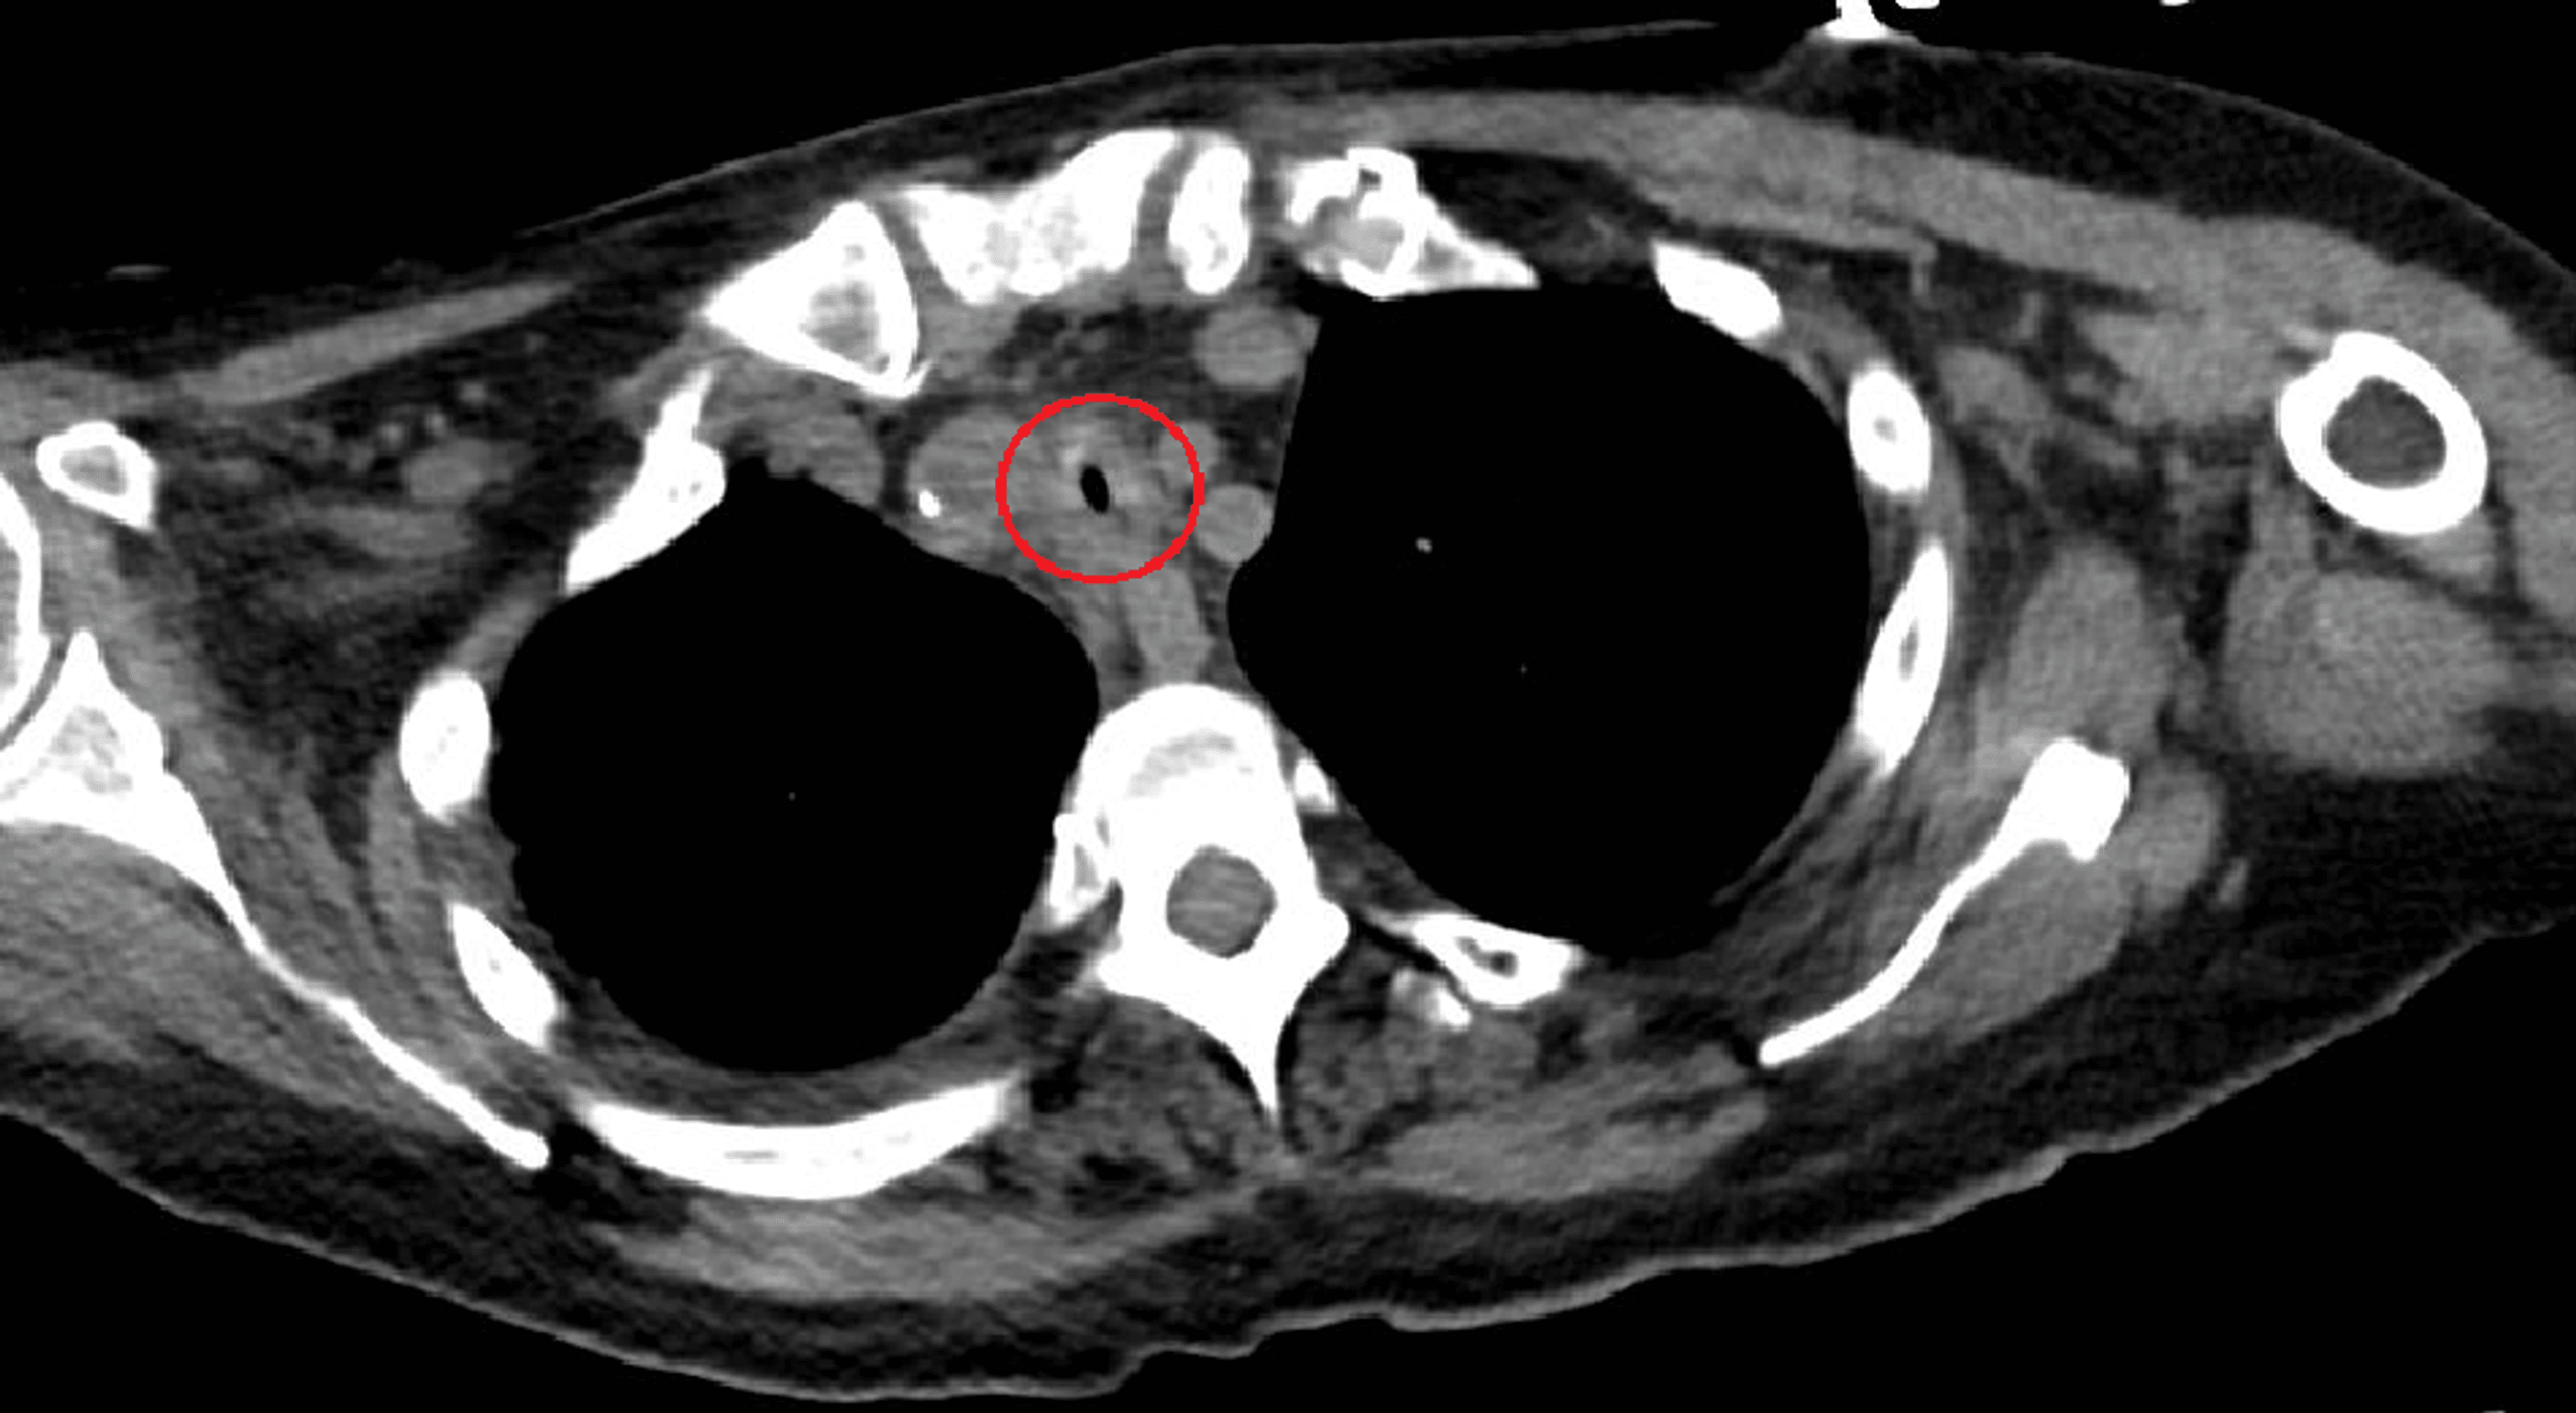

Postintubation Tracheal Stenosis Seminars in Thoracic and Cardiovascular Surgery

Post Intubation Tracheal Stenosis Tracheal Stenosis Pathophysiology laryngotracheal stenosis (lts) is a narrowing of the upper airway between the. causes of tracheal stenosis. tracheal stenosis occurs from the inferior margin of the subglottis to the carina,. tracheal stenosis is a narrowing of your trachea, or windpipe, due to the formation of scar tissue or. While most breathing issues are caused by lung problems,. Tracheal Stenosis Pathophysiology.

Severe longsegmental tracheal stenosis noted by multislice CT scan.... Download Scientific Tracheal Stenosis Pathophysiology tracheal stenosis is a narrowing of your trachea, or windpipe, due to the formation of scar tissue or. Most commonly tracheal stenosis is a result of an injury or illness such as: While most breathing issues are caused by lung problems, sometimes there is a problem. causes of tracheal stenosis. tracheal stenosis is narrowing the trachea that. Tracheal Stenosis Pathophysiology.